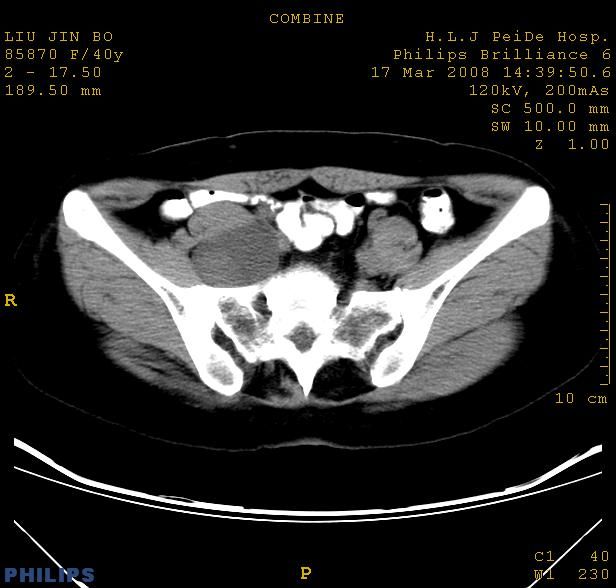

以下是引用qiuleiyu在2008-4-27 12:36:00的发言:[br]支持;右侧腰大肌后方神经源性肿瘤可能大,神经节细胞瘤?

以下是引用形影不离在2008-4-27 14:11:00的发言:[br]1.考虑右侧腰大肌脓肿。[br]2.左侧附件区炎症。[br]3.子宫增大,建议:进一步检查。